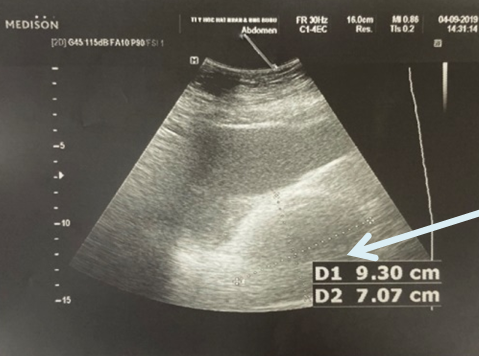

-        Siêu âm ổ bụng: Khối u vùng hố chậu trái kích thước 9,3x7cm

Hình 2. Hình ảnh khối u vùng tiểu khung trên siêu âm ổ bụng (mũi tên)